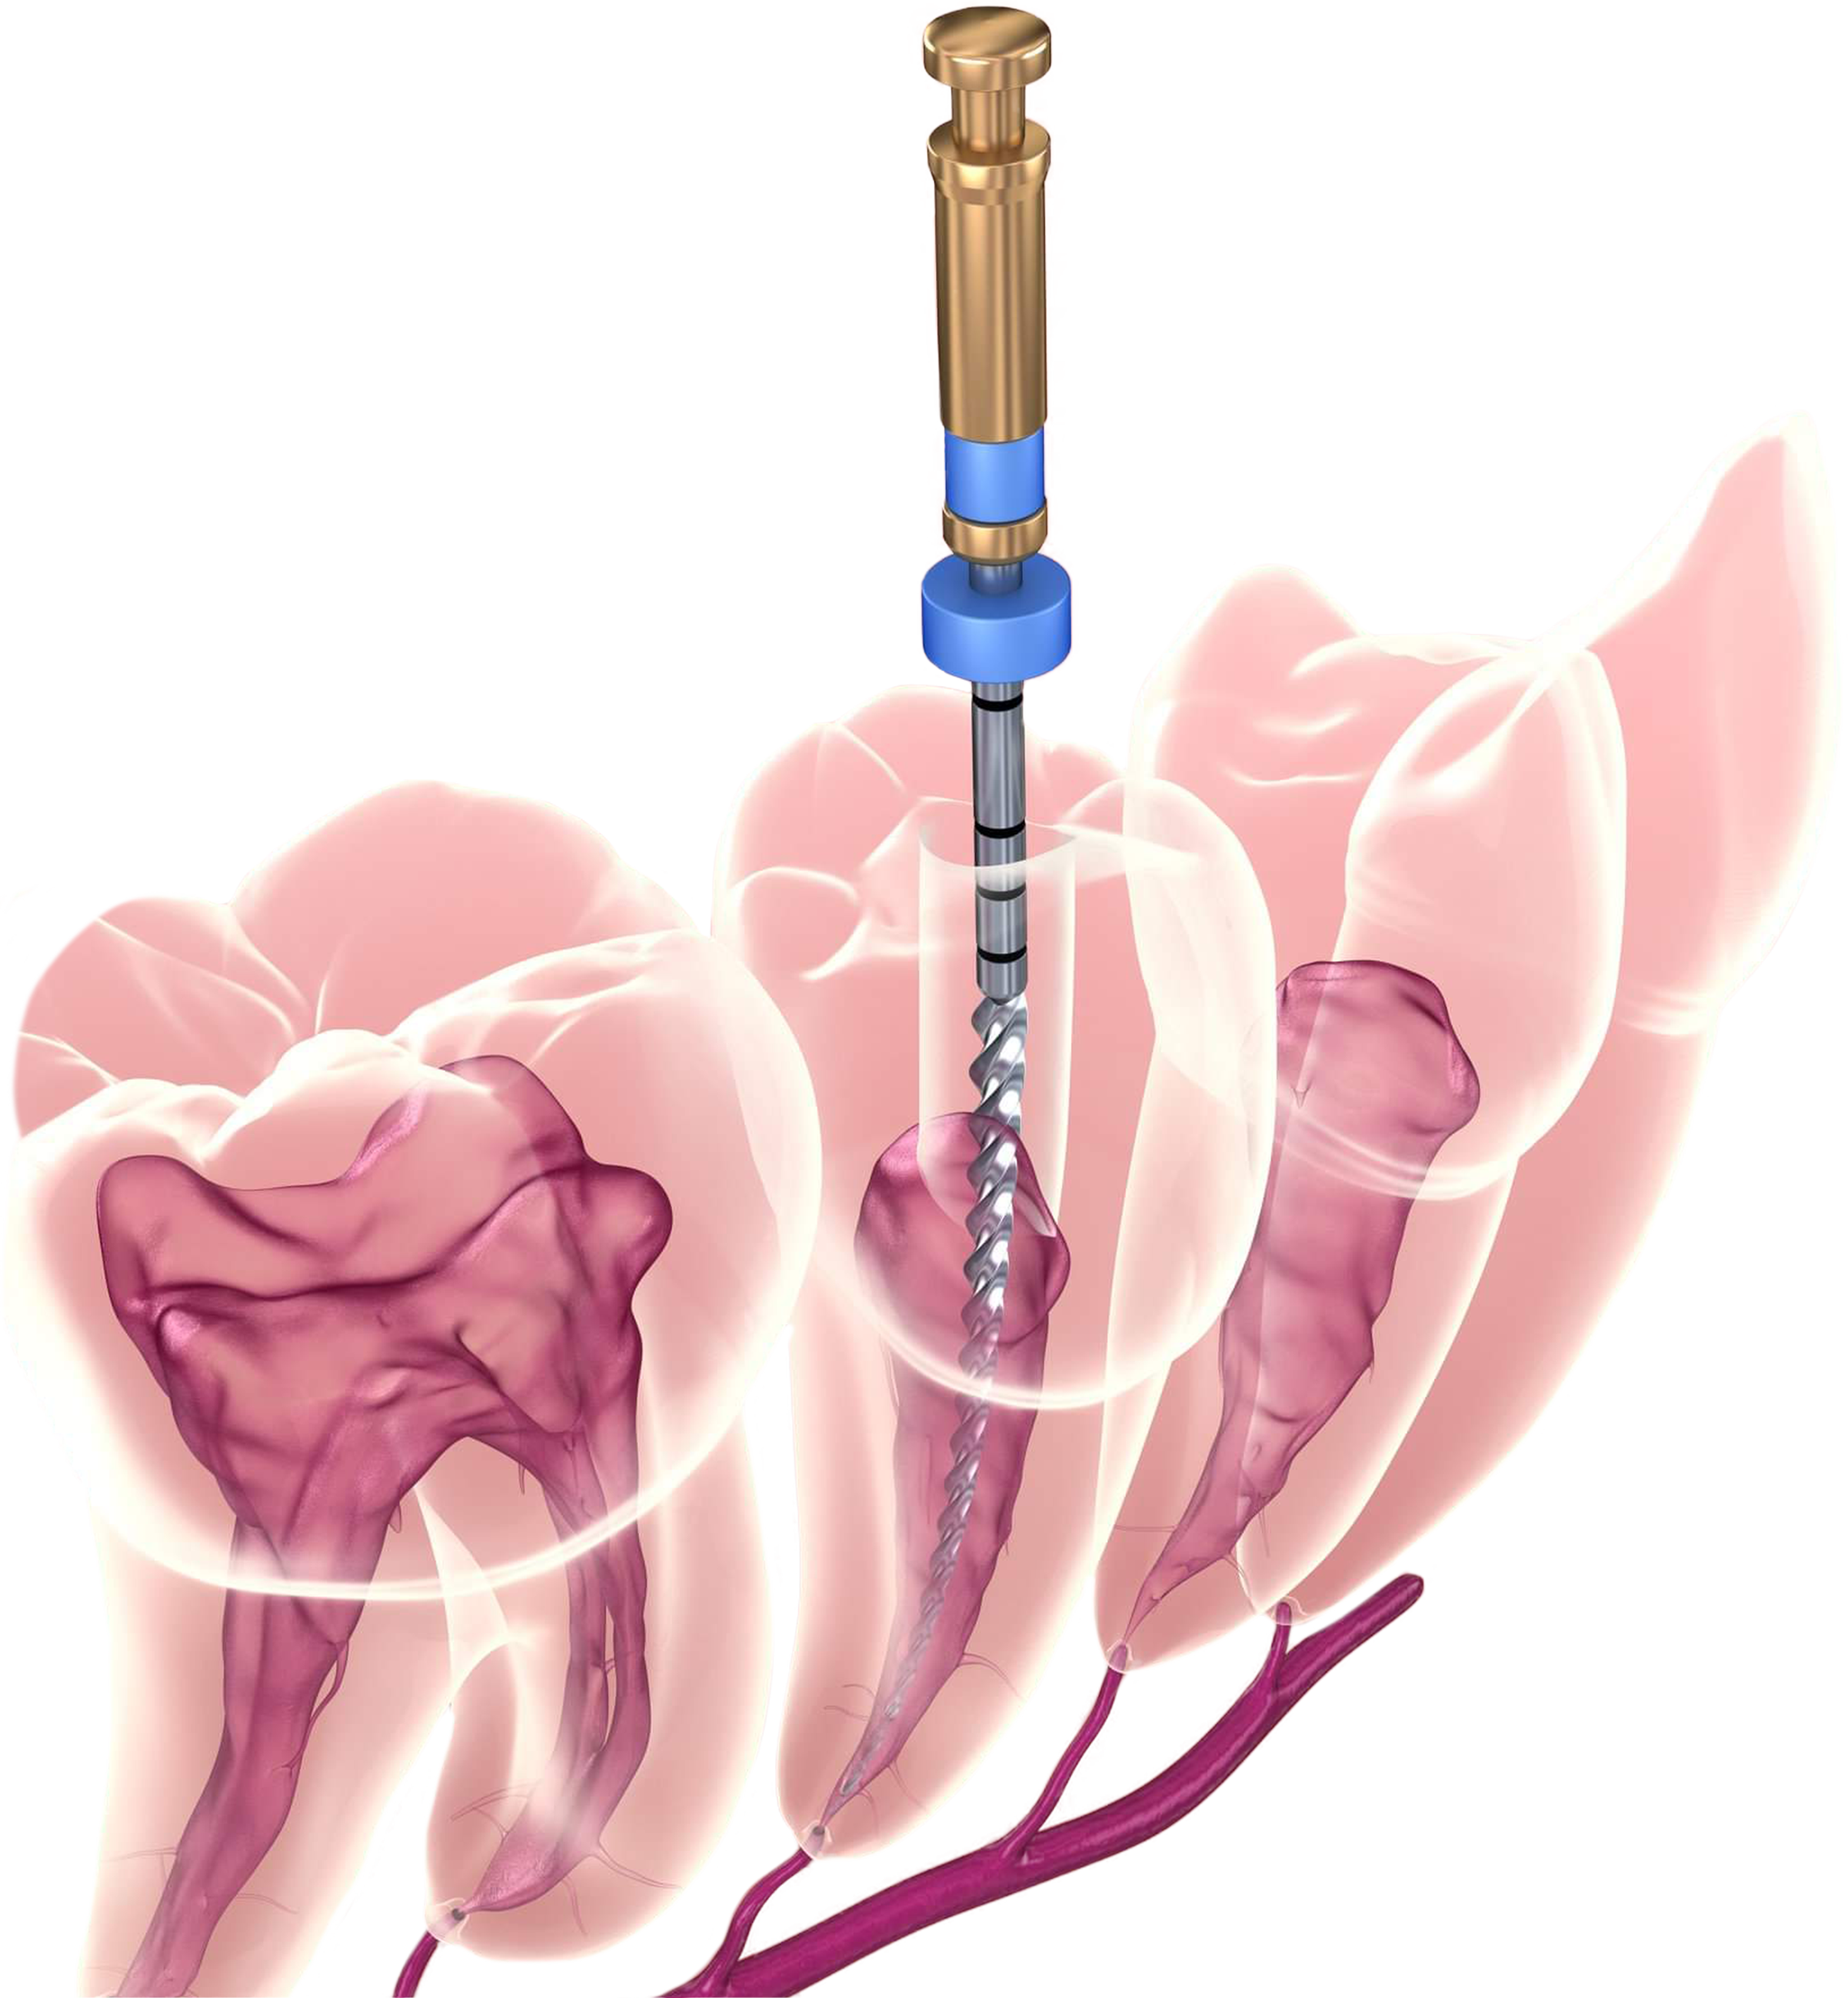

La endodoncia o tratamiento de conductos radiculares es un procedimiento conservador que consiste

en la extracción total o parcial de la pulpa lesionada de un diente y el sellado del conducto pulpar.

La pulpa del diente es un pequeño tejido blando que contiene los nervios y vasos sanguíneos.

Se encuentra en la parte más interior de la pieza dental y comunica ésta con el hueso maxilar.

Además de ayudar a formar el diente, la pulpa sirve para percibir estímulos externos.